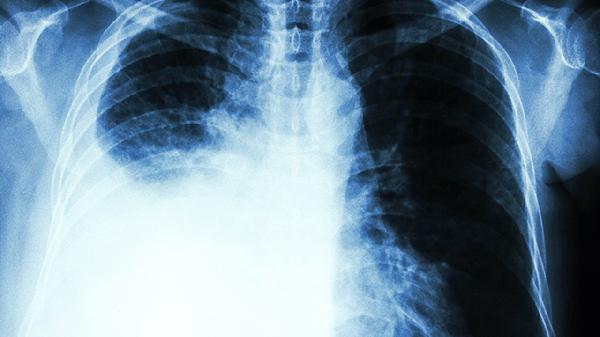

肺癌晚期的治疗方案有哪几种

肺癌晚期治疗以延长生存期、提高生活质量为目标,主要采用综合治疗手段,包括靶向治疗、免疫治疗、化疗及姑息治疗等。